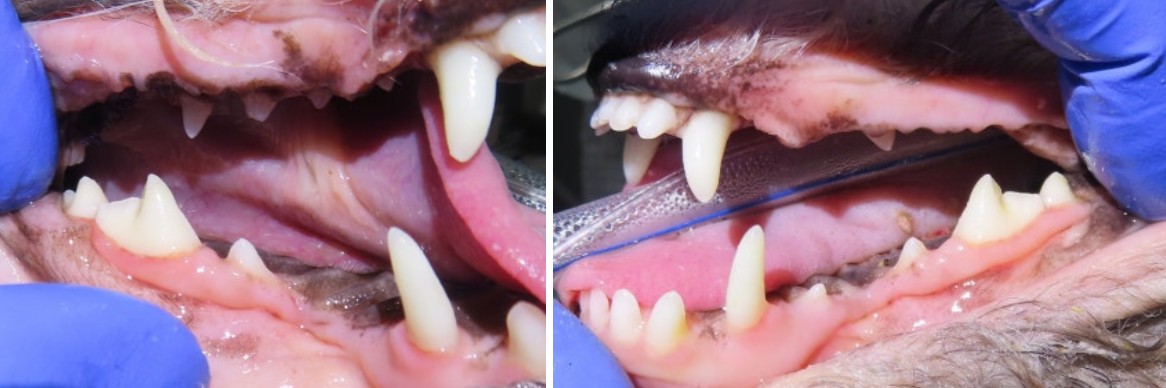

강북구 쌍문동 동물병원 비아츠에서는 양측 상악 M1을 치근 분리 후 단계적으로 제거하는 방식으로 발치를 진행했습니다.

대구치는 뿌리가 2개로 나뉘어 있고 치조골 소실이 동반된 경우 난도가 높은 치아입니다.

치근을 하나씩 분리하여 제거하고 잔존 치조골을 정리한 뒤 조직을 긴장 없이 봉합하는 방식으로 마무리했습니다.

양측 발치를 통해 통증에서 벗어났고 현재 정상 식사가 가능합니다.